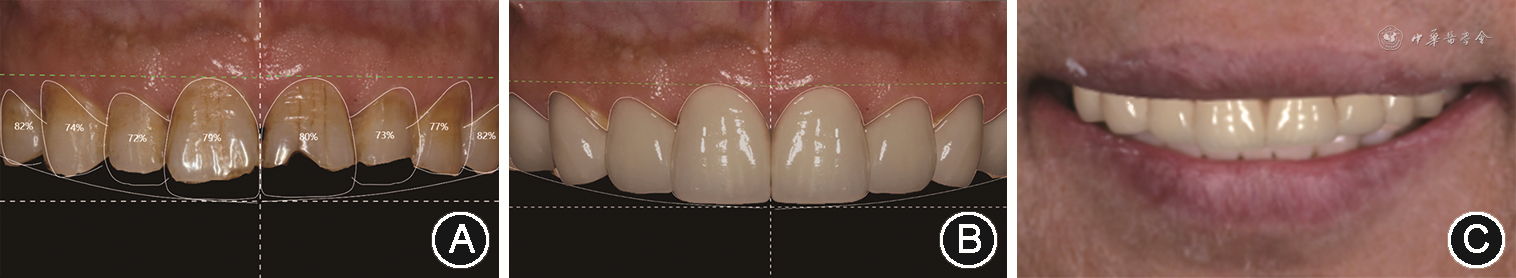

(2)美学重建设计:借助数字化微笑设计(digital smile design,DSD),综合分析患者微笑时上中切牙暴露量及牙冠美学比例,确定上前牙切缘位置,改善前牙宽长比例及微笑曲线(图5)。